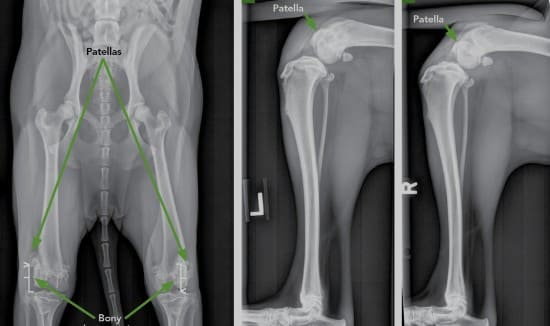

오늘은 우리 강아지들에게 정말 중요한 주제인 '강아지 슬개골 탈구'에 대해 이야기하려고 해요. 강아지를 키우면서 가장 큰 걱정 중 하나는 강아지의 건강과 행복일 텐데요, 특히 강아지의 슬개골 탈구는 소형견에서 자주 발생하며, 그로 인해 강아지가 겪는 고통은 무시할 수 없습니다. 그래서 오늘은 강아지 슬개골 탈구의 원인과 그 해결책에 대해 자세히 알아보고, 우리 강아지들이 건강하게 지낼 수 있도록 함께 공부해보려고 해요.

슬개골 탈구는 그 심각성에 따라 1단계에서 4단계로 구분되며, 각 단계에 따라 치료 방법도 달라집니다. 초기 단계의 슬개골 탈구는 비수술적 치료로 관리할 수 있지만, 심각한 단계에서는 수술이 필요할 수 있습니다. 수술 후에도 강아지가 안정적으로 회복할 수 있도록 꾸준한 재활치료와 관리가 필요합니다.